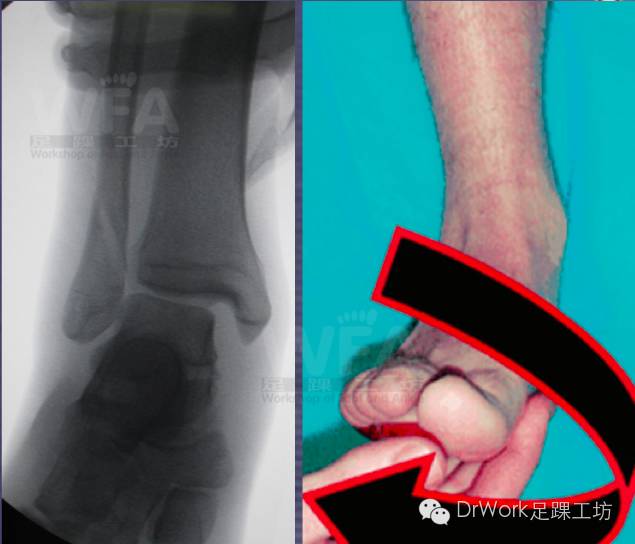

外旋应力试验

术中Hook试验

• 目前最佳诊断方法

• 矢状面移位较冠状位移位更显著

• 100N左右外力较合适

• 过大未提高准确率

• TFCS>5mm即可诊断不稳